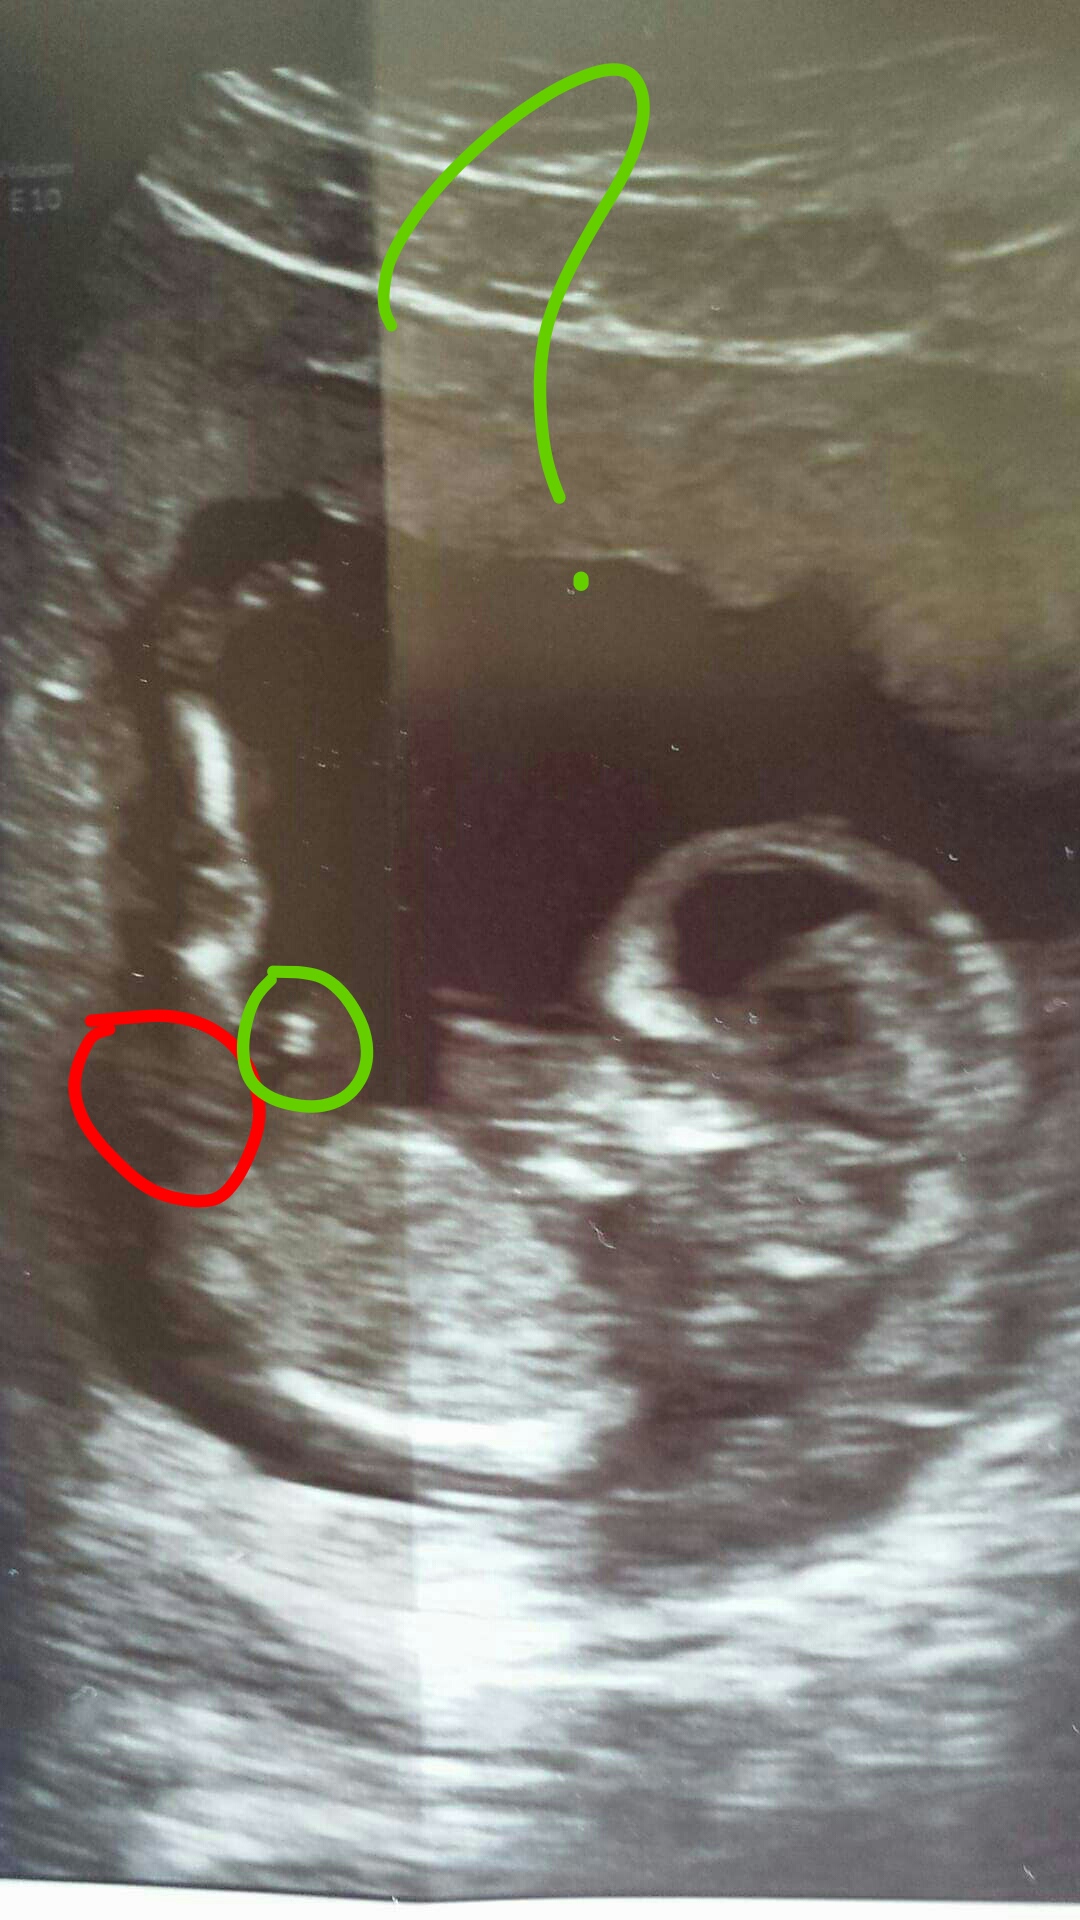

HELP! Keen eyes needed! Idk where to look! 13w1d

Attachment 31647

Can anyone shed any light? Is there a nub pictured in this or is the leg in the way? I'm also not sure where to look or what I'm looking at haha and I haven't had any luck posting in other forums or Facebook pages! I've been told there isn't a clear nub but I still don't know where it is or if they mean they can't see it at all. Any and all guesses/opinions welcomed! This is from my 13w1d scan.THANK YOU!

*UPDATE* I was told the red circle is the cord by someone in another group that used to gender ID before studying nub theory. She did not guess, however. So, idk.